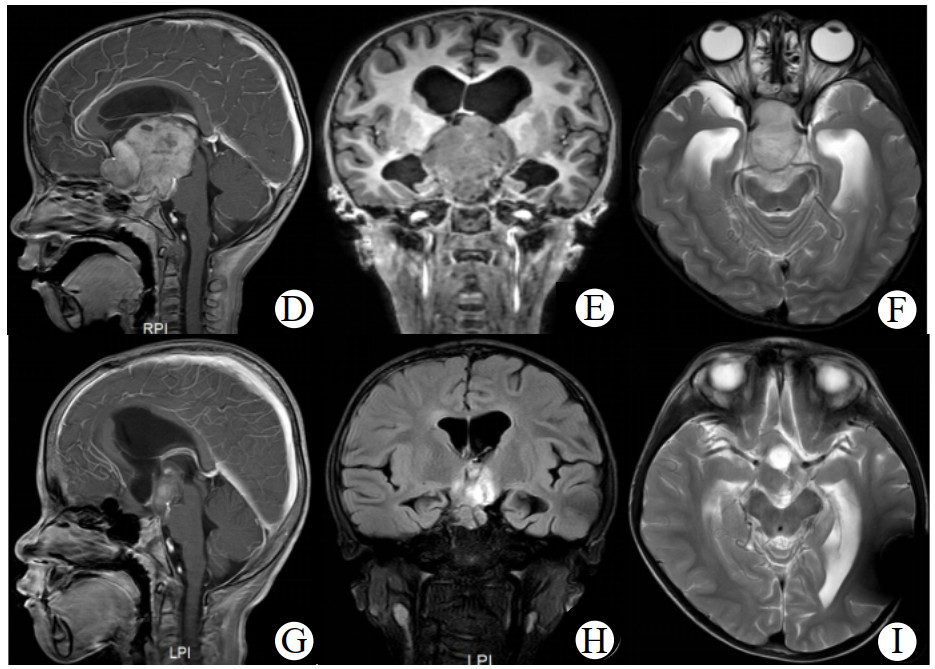

病例1、3、4术后复查肿瘤体积缩小分别为20%、11.7%、42.0%,术后予CV方案化疗,并分别在化疗14个月、8个月、12个月复查较术后肿瘤体积再次缩小10.5%、35%和45.0%。病例2术后拒绝化疗,随访1.5年后复发行2次手术,术后予CV方案化疗结束9个月再次复发,查BRAF基因示KIAA1549-BRAF融合,予靶向药物(曲美替尼片)治疗9个月复查头颅MRI示肿瘤体积较前基本相仿。病例5术后予CV方案联合贝伐珠单抗治疗14个月,化疗结束时复查头颅MRI示肿瘤(2.5 cm×2.4 cm)体积较术后缩小65%,随访25个月复查肿瘤体积(2.8 cm×3.3 cm)较化疗结束时增大54%。其中病例4患儿手术+CV方案治疗后肿瘤体积缩小最明显(图 2)。

| 注:术前(D、E、F)与化疗12月(G、H、I)头颅增强MRI:D、E、F可见鞍上区类圆形混杂团块影(5.3 cm×5.2 cm),肿块稍长T1信号增强后明显强化,囊性T1、T2信号影增强后未见强化,视交叉显示不清,肿块后缘紧贴脑干;G、H、I可见鞍上区肿块较前缩小(2.8 cm×3.5 cm),呈稍长T1稍长T2,内见小囊性长T1长T2信号影,增强后肿块明显强化 图 2 病例4患儿术前及化疗后头颅MRI影像对比 |